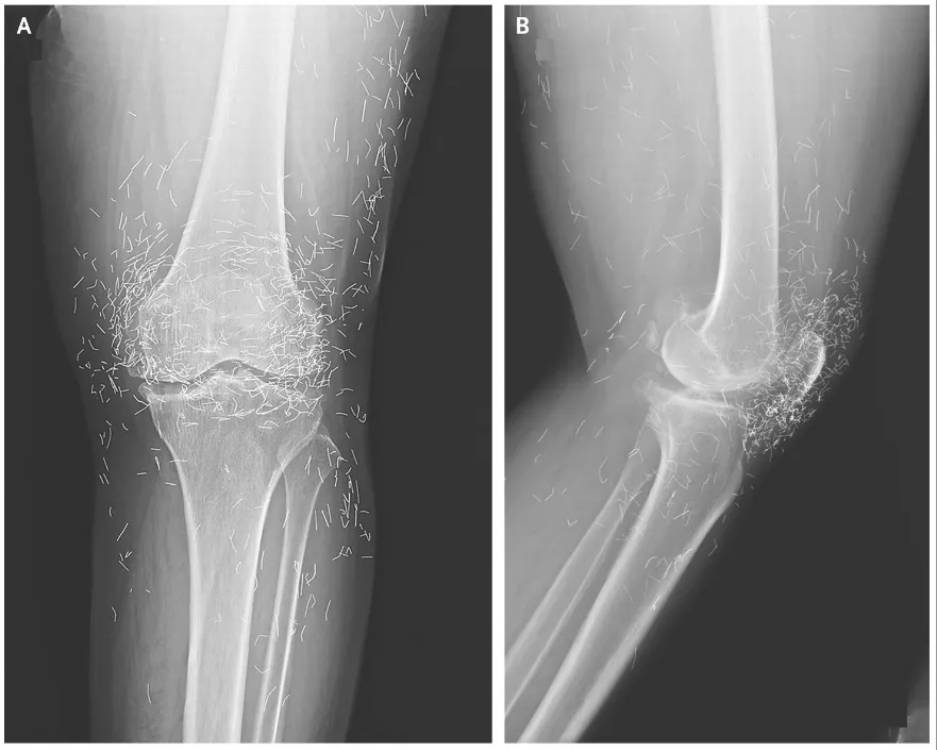

Finalement, ses genoux lui faisant trop mal, elle est retournée à l’hôpital. Les médecins lui ont fait passer une radio. Et là, surprise ! En plus des signes classiques de l’arthrose (os épaissis, petites excroissances osseuses), ils ont vu des centaines de petites lignes très fines et brillantes, comme des paillettes, tout autour de l’articulation de son genou. Après enquête, il s’est avéré que c’étaient de minuscules fils d’or.

Les médecins ont rapidement compris. Ces fils d’or avaient été insérés lors de ses séances d’acupuncture. Il s’agit d’une technique spécifique où de courts fils d’or stériles sont volontairement laissés sous la peau, à l’emplacement des points d’acupuncture. L’idée est que ces fils continuent de stimuler les points en permanence, même après la séance, pour un effet antidouleur prolongé. Cette pratique, connue sous le nom d’acupuncture aux fils d’or, est assez courante en Asie pour traiter l’arthrose.